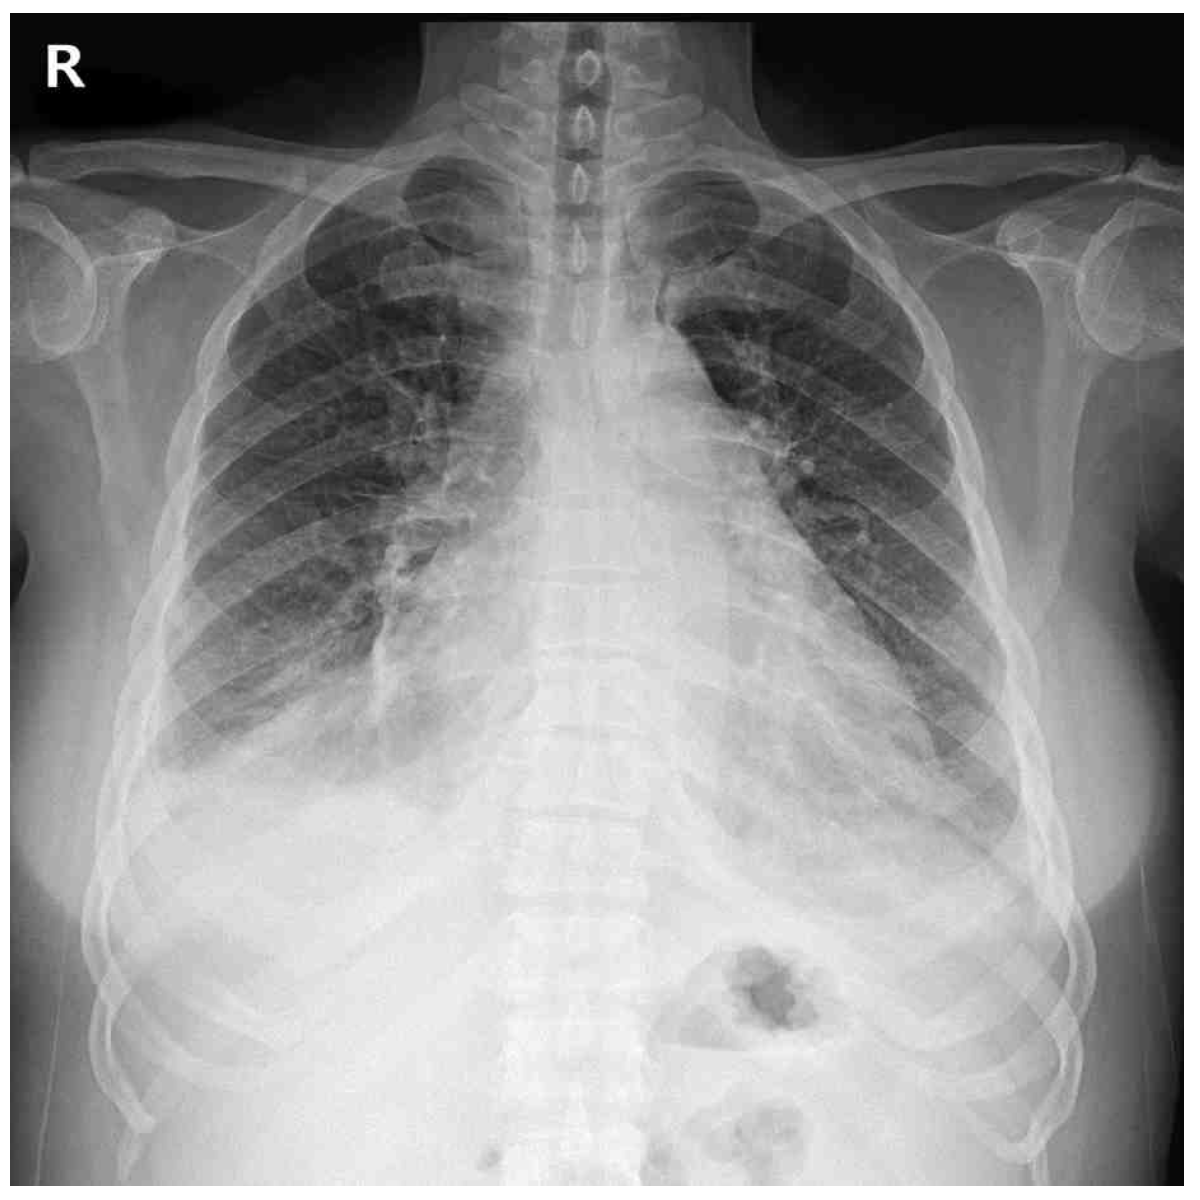

34세 여자가 1주 전부터 양쪽 다리가 붓고 숨이 차서 병원에 왔다. 1주 전에는 빨리 걸을 때에만 숨이 찼으나 지금은 평지를 조금만 걸어도 숨이 찬다고 한다. 1년 전부터 가슴이 두근거리고 손이 떨리며 더위를 참지 못하고, 체중이 10kg 줄었다고 한다. 혈압 120/70 mmHg, 맥박 120회/분, 호흡 20회/분, 체온 36.9 C이다. 앞목은 부어있고 압통은 없다. 심잡음은 들리지 않고 양쪽 등아랫부분에서 거품소리가 들린다. 양쪽 정강뼈앞 오목부종이 있다. 가슴 X선사진과 심전도이다. 검사는?

CXR: Cardiomegaly, pulmonary edema

• 한편, BLLF rale과 pretibial pitting edema, CXR상의 cardiomegaly와 pulmonary edema, ECG상 LVH 등 심부전을 시사하는 소견들이 관찰되는데, 갑상샘중독증에서는 심장에 부하가 증가하며 보상작용을 상실하면 심부전이 발생할 수 있다.